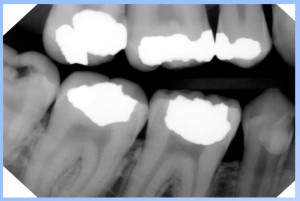

CDR Elite-Schick

Hard to find information on the sensor

Kodak RVG6100

-20 lp/mm

Gendex Sensor

QuickRay Sensor Image